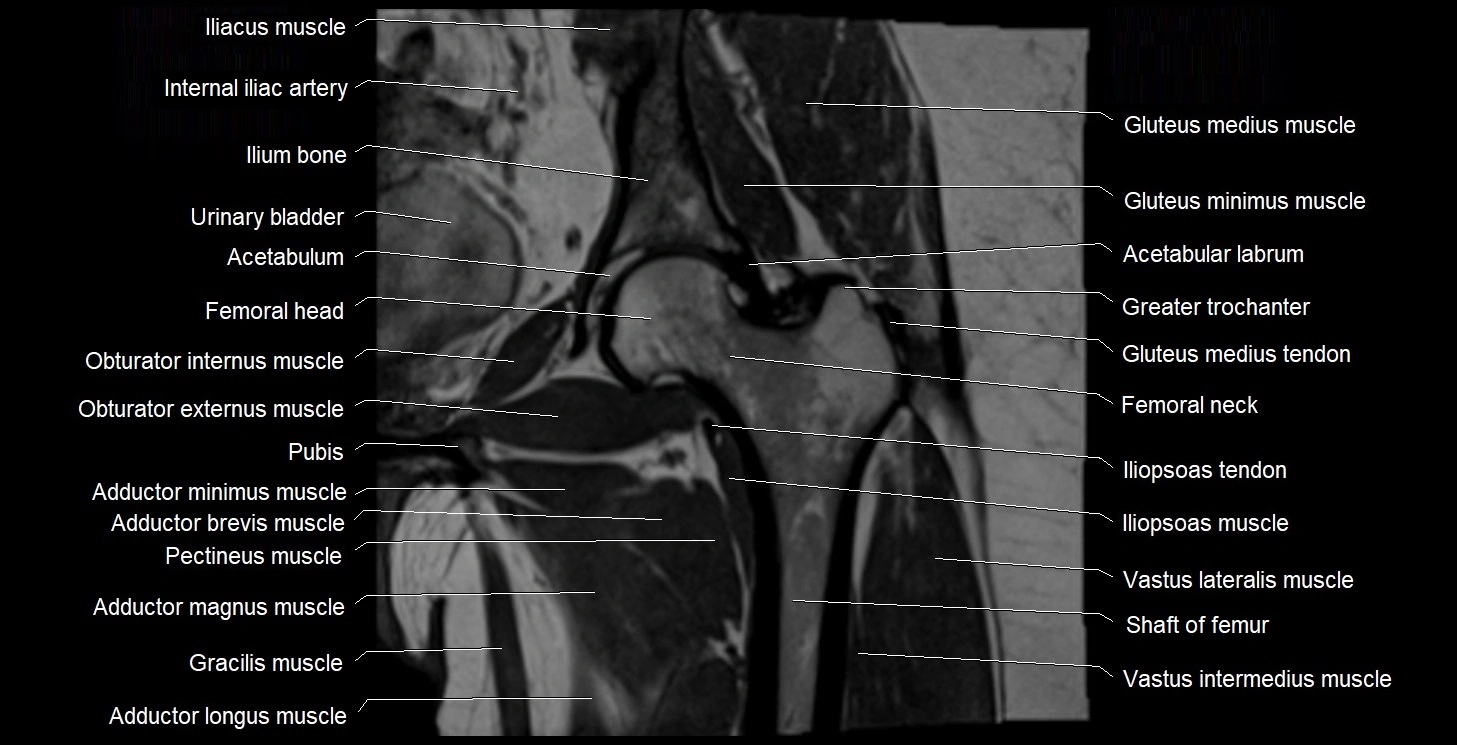

- Acetabular labrum

- Acetabulum

- Adductor brevis muscle

- Adductor longus muscle

- Adductor magnus muscle

- Adductor minimus muscle

- Gluteus medius muscle

- Gluteus medius tendon

- Gluteus minimus muscle

- Gracilis muscle

- Greater trochanter

- Head of femur

- Iliopsoas muscle

- Iliopsoas tendon

- Ilium bone

- Internal iliac artery

- Levator ani muscle

- Neck of femur

- Obturator externus muscle

- Obturator internus muscle

- Pectineus muscle

- Pubic bone

- Rectus femoris muscle

- Urinary bladder

- Vastus intermedius muscle

- Vastus lateralis muscle